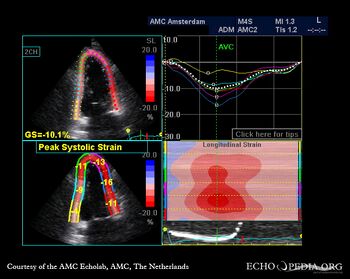

A3CH: akinesia of basal posterior wall A4CH: strain image

E00522.jpg

E00523.jpg

A2CH: strain image A3CH: strain image